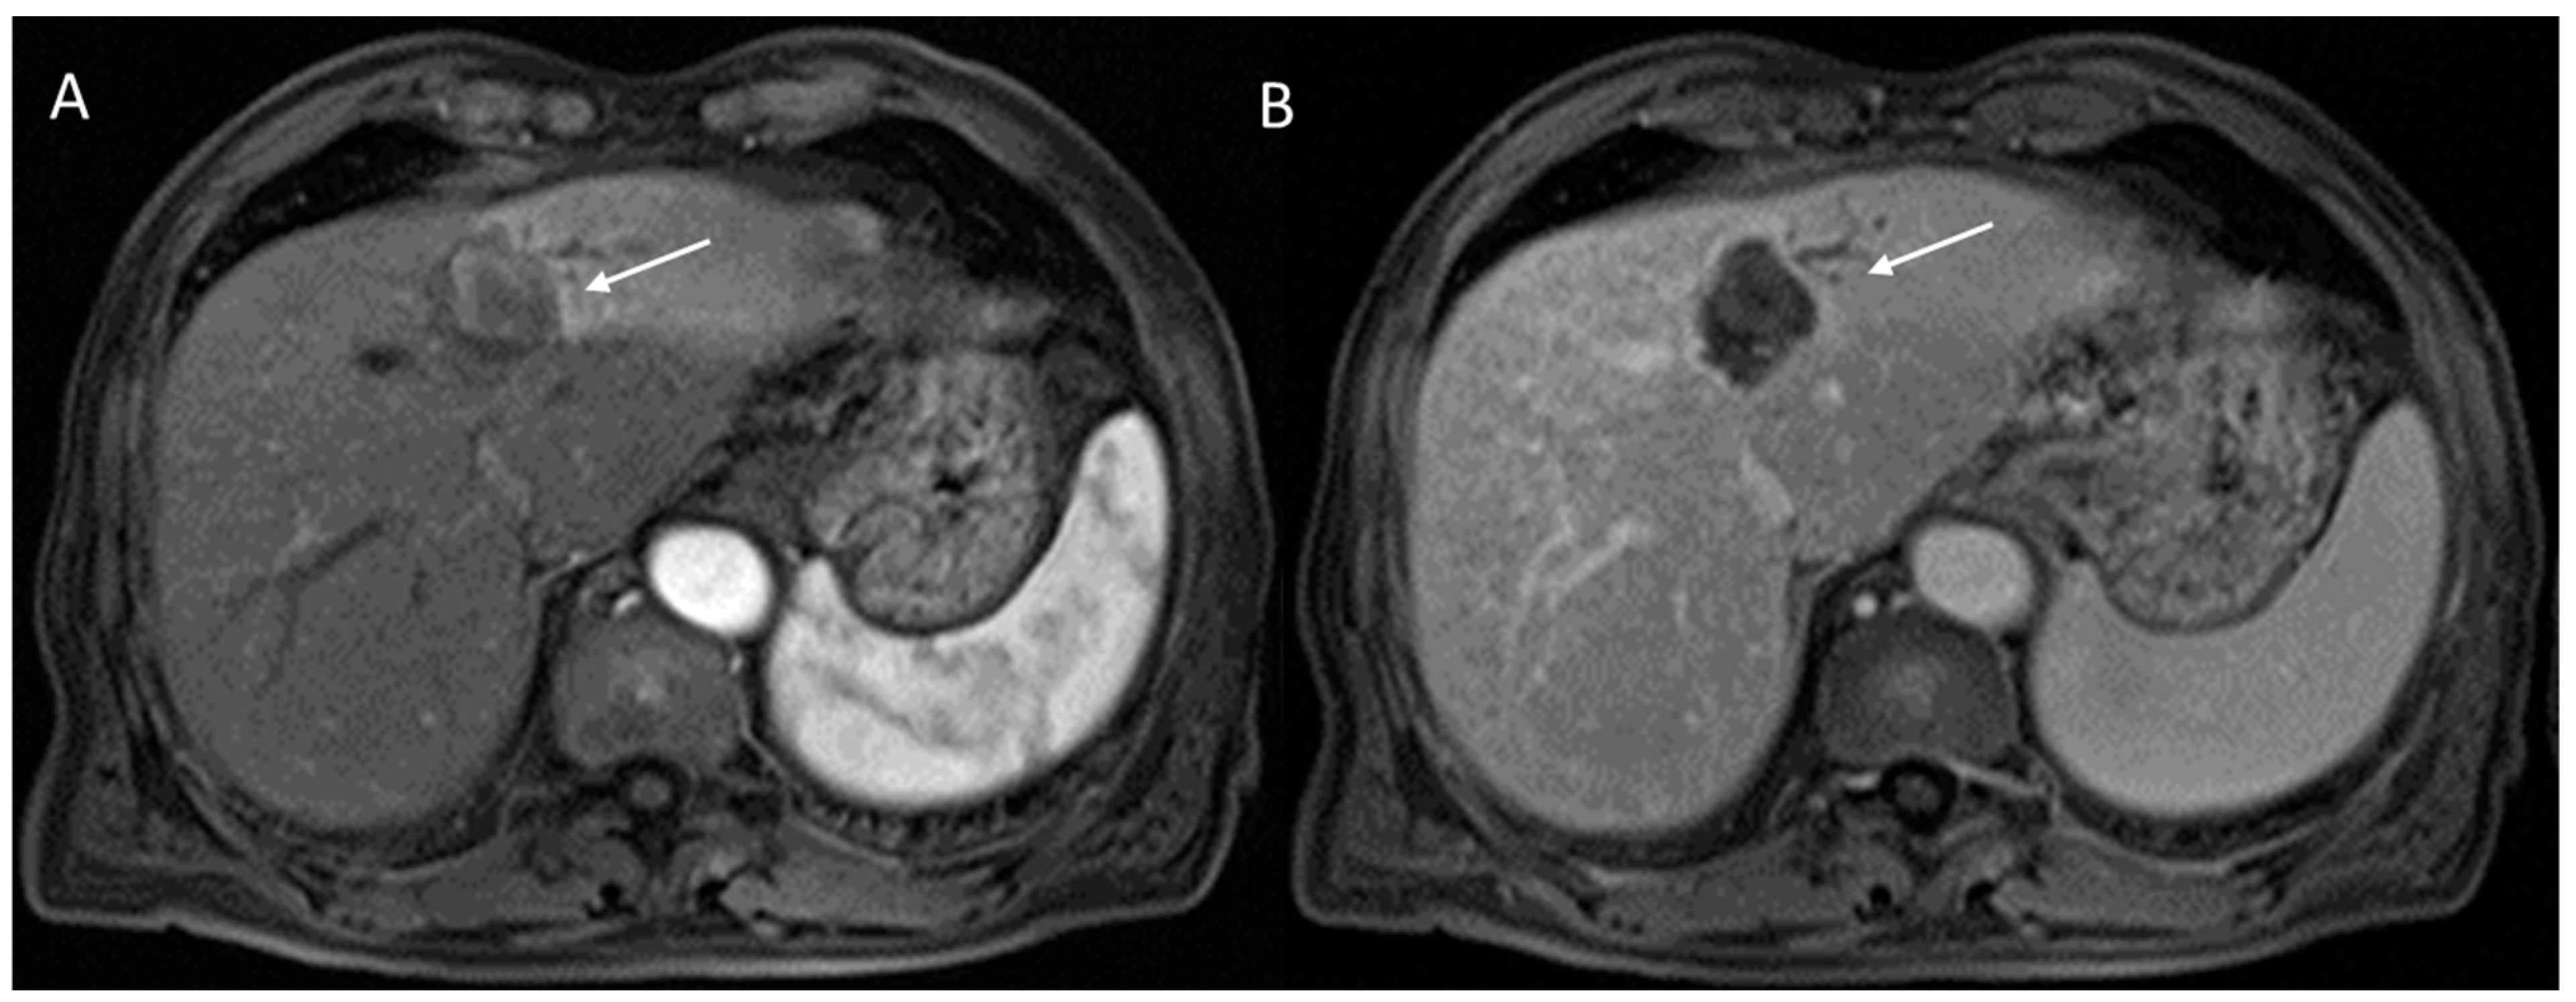

2.2.5. LR-M Category